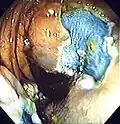

The first step is usually a digital rectal examination (DRE), to examine the tone of the anal sphincter and to determine if preparation has been adequate. A DRE is also useful in detecting anal neoplasms and the clinician may note issues with the prostate gland in men undergoing this procedure.[57] The endoscope is then passed through the anus up the rectum, the colon (sigmoid, descending, transverse and ascending colon, the cecum), and ultimately the terminal ileum. The endoscope has a movable tip and multiple channels for instrumentation, air, suction and light. The bowel is occasionally insufflated with air to maximize visibility (a procedure that gives the patient the false sensation of needing to take a bowel movement). Biopsies are frequently taken for histology. Additionally in a procedure known as chromoendoscopy, a contrast-dye (such as indigo carmine) may be sprayed through the endoscope onto the bowel wall to help visualize any abnormalities in the mucosal morphology. A Cochrane review updated in 2016 found strong evidence that chromoscopy enhances the detection of cancerous tumors in the colon and rectum.[58]